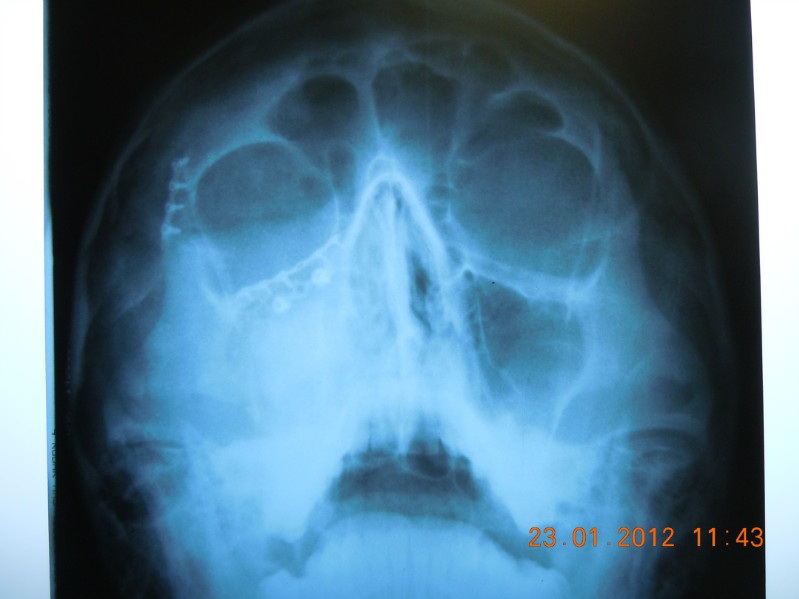

Остеосинтез скуловой

Остеосинтез скуловой 90 фото